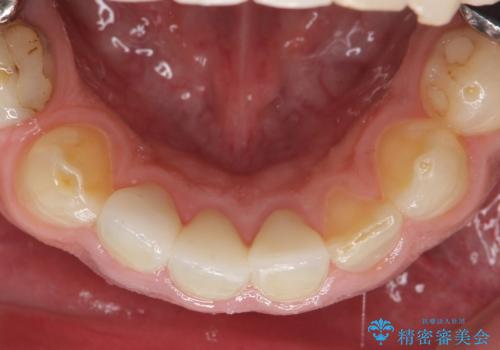

- 歯がない左側でものが咬めず、右側で咬むと歯が痛むので診て欲しいといらっしゃった方の症例です。

根尖病変が認められる歯は再根管治療を行い、歯根が破折していた左上4は抜歯しました。

インプラントは希望されなかったため、左側は1番から7番のロングスパンブリッジによる補綴を行いました。